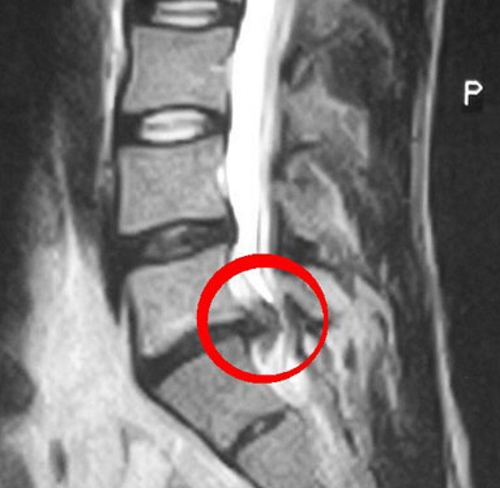

Ортопед назначит МРТ, чтобы иметь точное представление о размере и локализации грыжевого образования. Если есть необходимость, то возможно будет предложено хирургическое вмешательство.

- Первичный осмотр ортопеда, назначение обследования и анализов. Назначение МРТ поясничного отдела.

- Получение результатов исследования, которые дают точное описание расположения и объемов грыжи. Если выпячивание диска расположено сбоку позвоночного столба и доставляет болезненные ощущения, может быть принято решение о необходимости оперативного вмешательства.

Рост живота и изменение центра тяжести, вызванное характерной осанкой беременных, увеличивают весовую нагрузку на позвонки и, как следствие, имеющаяся патология диска прогрессирует. Помимо этого, на грыжу напрямую влияет изменение гормонального фона при беременности. На ранних сроках возросшая секреция прогестерона усиливает кровообращение в мелких сосудах и может способствовать отеканию нервных корешков.

Ближе к родам выработка релаксина приводит к расслаблению мышц и связок, вызывает ослабление мышечного корсета вокруг позвоночника и повышение нагрузки на позвонки. Также после 7-го месяца начинается активный рост матки, которая задней стенкой прилегает к позвоночнику и своим давлением на грыжевое выпячивание может спровоцировать ущемление нервных корешков.